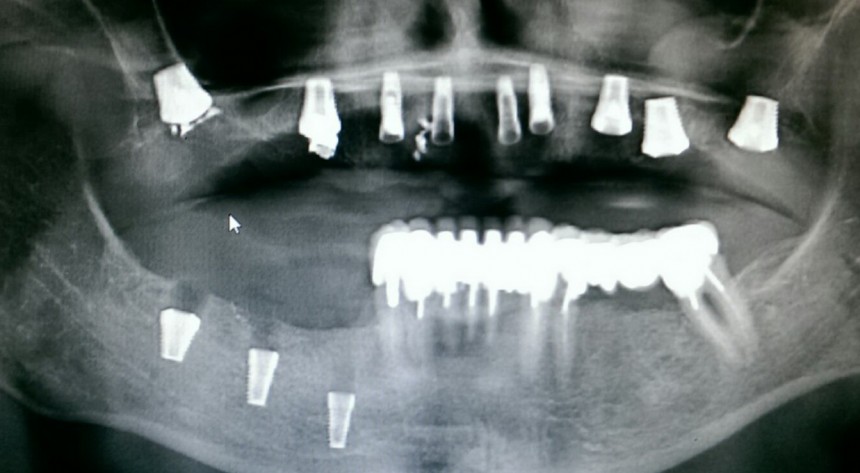

Случается чаще, чем можно представить. В основном, из-за убеждения ряда моих коллег в том, что конечная цель имплантологического лечения — это интегрированные импланты, а не протезирование на этих самых имплантах. Итог — ну вот, всё прижилось, пациент приходит к ортопеду, а тот разводит руками — типа, ничего не могу сделать. С одной стороны, ортопеда можно понять — на кривом фундаменте хороший дом не построишь. С другой стороны, некоторые имплантологи считают, что ортопеды просто неженки и лентяи, которым только подавай идеальные случаи. Особенно в создании данной проблемы отличаются некоторые челюстно-лицевые хирурги, не имеющие стоматологического образования:

То есть, хороший имплантолог мыслит больше как ортопед, а не как мясник челюстно-лицевой хирург.

Теоретически, у многих имплантационных систем существует возможность ортопедической компенсации неверно установленных имплантов — от переключения платформ до индивидуальных абатментов. Но даже такое не всегда возможно. Приходится удалять импланты и заново проводить имплантологическое лечение.